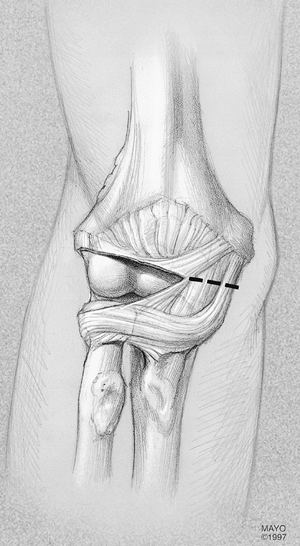

Figure 21-2. A,B:

If a simple “column” release is anticipated a limited incision measuring 6 to 8 cm in length is made over the lateral column, ending 2 cm distal to the lateral epicondyle as shown in this right elbow. |

ipsilateral extremity and the arm draped free and brought across the

chest. The proximal one-half of a Kocher incision, which extends 6 cm

proximal to and 3 cm distal to the epicondyle, is used if there is no

previous incision and if there are no symptoms related to the ulnar

nerve (Fig. 21-2). If there are symptoms